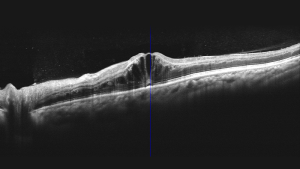

Режим глибокої судинної томографії (DCI)

Використання глибокої судинної томографії для виявлення неоваскуляризації судинної оболонки.